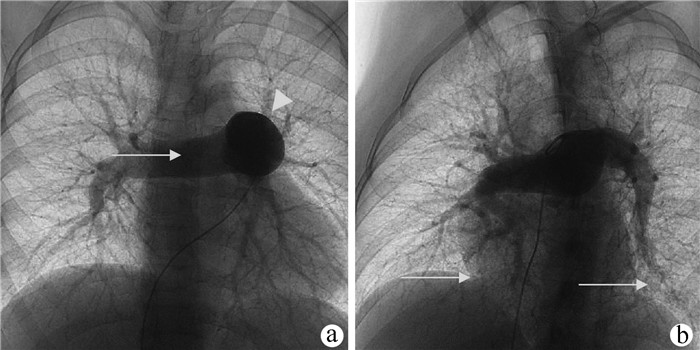

肝脏遗传性出血性毛细血管扩张症1例报告

王婷婷, 马亮, 陈建平

2022, 38(2): 423-425. DOI: 10.3969/j.issn.1001-5256.2022.02.032

摘要(1110) HTML (367) PDF (2696KB)(54)

摘要: